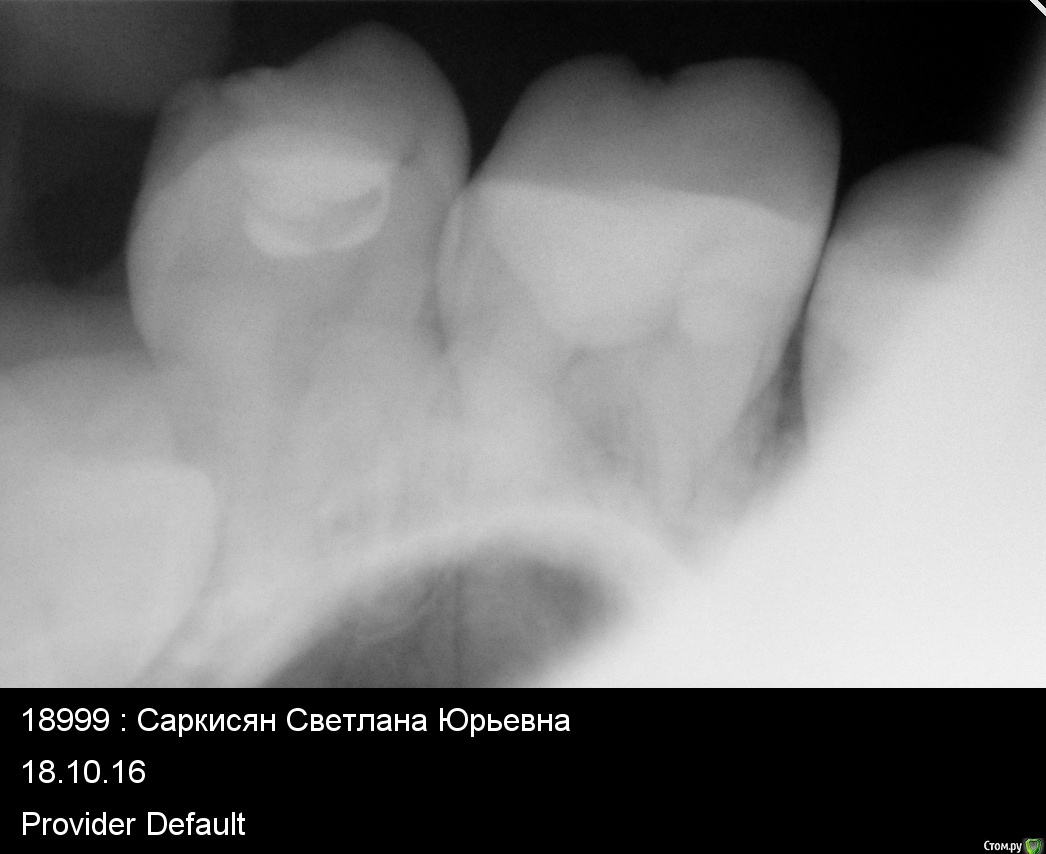

Setasy Опубликовано 14 декабря, 2016 Поделиться Опубликовано 14 декабря, 2016 (изменено) Здравствуйте! Очень нужен совет. В июле мне пролечили глубокий кариес 6-ки сверху слева. Примерно в то же время лечили и 6-ку снизу, там никак не могли подобрать нормально пломбу, больно было на ней жевать, пока не поставили ветример. Таким образом, я не могла полноценно кушать на левой стороне и проверить, все ли в порядке с верхним 6 зубом. Когда наконец смогла это делать, стала ощущать постоянный дискомфорт при жевании твердой пищи ближе к 5 зубу. Обратилась к другому доктору, он снял пломбу, думали, может что-то проседает там, ничего не изменилось. Когда он снял в следующий раз всю реставрацию, сказал, что видит там трещину корня, но не был уверен. У меня в тот же день начался острый пульпит, сильнейшая боль. Каналы мне врач пролечил, с коффердамом, с бинокулярами, все как положено, заложил кальций. Но есть на зубе по-прежнему невозможно было. Так не болит, но даже минимальная нагрузка (мягкой пищей) и все, чувствуется языком снова боль, неприятно дотрагиваться. Врач от меня отказался, говорит, что все правильно делает и не знает, почему у меня не проходит. Наверное все-таки трещина, тогда любое лечение несостоятельно. Обратилась еще к одному врачу, она рассверлила временную пломбу, промыла хлоргексидином каналы и заложила какую-то йодовую пасту. Трещины не увидела. После этого вообще до зуба не дотронуться было, все вокруг было очень болезненно и как будто камней наложили. На 4 день это острое состояние прошло и вернулось все то же, что и было. До зуба больно дотрагиваться языком и невозможно есть. Сегодня мне сделали КТ. Врач, смотревший КТ, сказал, что трещины корня не видит (хотя я прочла, что трещину корня по КТ вообще нельзя увидеть). Якобы надо расширять каналы. Что имелось ввиду, непонятно. Каналы мне точно лечили хорошо (4 штуки нашли). КТ прилагаю https://yadi.sk/d/_2x90byG33Wtt8 Снимки есть до лечения каналов. Прикладываю...и также ортопонарама. Я планирую беременность и мне хочется как можно быстрее разобраться с этим зубом. Можно ли оставить пока так как есть (допустим, если там трещина все-таки) или необходимо удаление? Если удалять, возможно ли сразу поставить имплант при удалении или нужно ждать? Ну и вообще хотелось бы услышать мнение по поводу ситуации, что может быть и что делать. Спасибо!!!!!!!! Изменено 14 декабря, 2016 пользователем Setasy Ссылка на комментарий